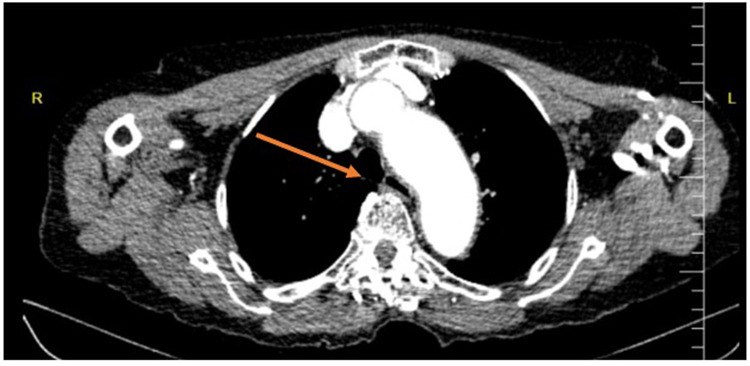

Case presentation: The patient presented with chest discomfort, dyspnea, and dysphagia for liquids and solids. Imaging revealed esophageal compression due to ascending aorta dilation. The dysphagia persisted despite pharmacological management, leading to the decision that surgical intervention was too risky. We placed a percutaneous endoscopic gastrostomy (PEG) tube to maintain nutrition, stabilizing her condition and improving her quality of life.